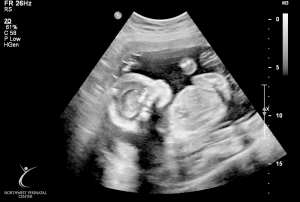

Last Ultrasound